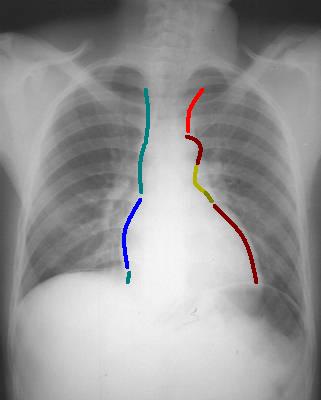

Cliche de face PA :

le cliché de face PA à droit il y avait troi arc et à gauche

avaient 4 arc , ce sont :

| A droite , le

bord du mediastin est veineux :

Arc superieure droit :

tronc veineux brachiocephalique

Arc moyen : veine cave

superieure

Arc inferieure ,convexe:

Oreillette droit et veine cave inferieure

A gauche , le bord du

mediastin est arteriel : - artere

sous-claviere gauche

- Arc superieure ( bouton

aortique )

- Arc moyen : infundibulum arteriel

pulmonaire et auricule gauche

- Arc inferieure , convexe : bord

gauche du ventricule gauche .